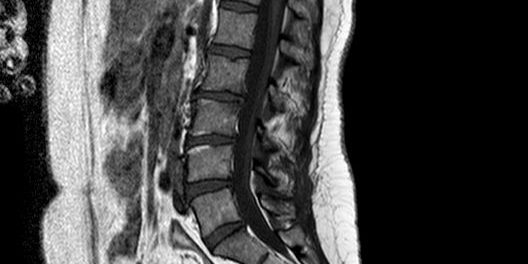

Ed è qui che entra in gioco la piccola modifica alla metodologia di impostazione degli esami, perchè ho deciso su molti protocolli di effettuare la sequenza ponderata in T1 (la maggiorparte TSE) come prima sequenza.

- Mi permette comunque di valutare bene l’osso e tutti gli spazi adiposi (se c’è una sostituzione patologica la vedo)